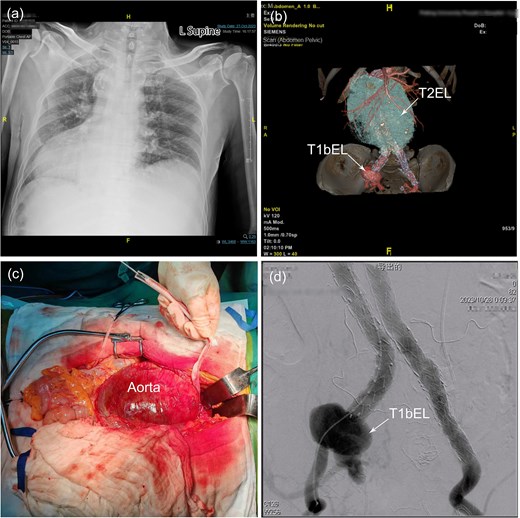

A 60-year-old male patient with a known medical history of hypertension and SIT was admitted to the hospital due to progressively worsening low back pain. Of particular note, the patient had undergone EVAR with aorto-iliac endograft for a ruptured AAA at the local hospital 5 years prior to this admission. Upon initial evaluation, a routine physical examination revealed the presence of a palpable, pulsatile abdominal mass at the level of the umbilicus. Chest radiograph confirmed dextrocardia (Fig. 1a). Contrast-enhanced computed tomography (CT) imaging revealed the presence of a previously placed stent–graft, a type II endoleak (T2EL) associated with a significantly enlarged aneurysm sac, a dilated distal right CIA with a type Ib endoleak (T1bEL) (Fig. 1b). Additional findings included multiple hepatic cysts, bilateral renal cysts, and cholelithiasis.

(a) Chest X-ray shows dextrocardia and dilation of the mediastinal shadow. (b) Contrast-enhanced computed tomography demonstrated a previous stent–graft placement, a type II endoleak with a giant aneurysm sac, a distal right common iliac artery dilatation with a type Ib endoleak. (c) Identification of a huge infrarenal aortic aneurysm through a mid-abdominal incision and was subsequently controlled with a sleeve to facilitate subsequent surgical procedures. (d) Angiography revealed a significant type Ib endoleak in the distal to the right common iliac branch. AA, abdominal aorta; CIA, common iliac artery; LRA, left renal artery; RRA, right renal artery; T1bEL, type 1b endoleak.